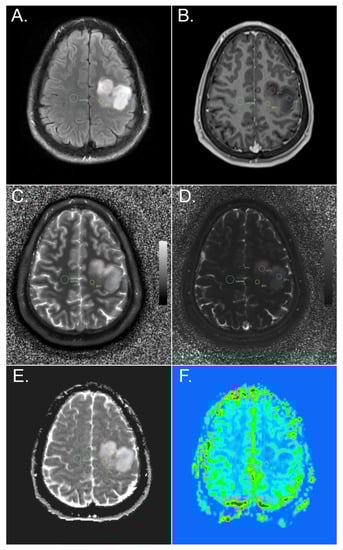

2.3. Region-of-Interest (ROI) Evaluation